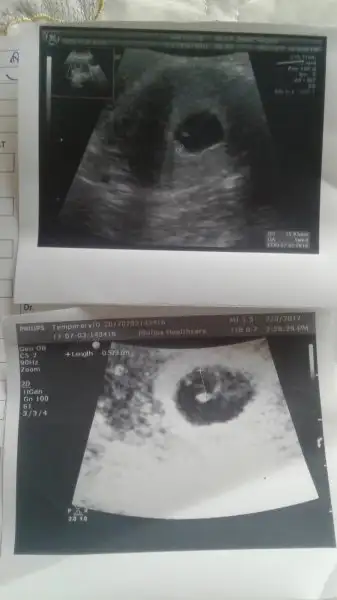

Allh razi olsun ama ne yazikki iyi haber ler alamadım pazartesi belli olack herseyEsr02 merhaba canım kaç gündür bakıyordum yazdıklarına dua ettim hep senin için insalah bebeğin seninledir diye bugün de doktora gittin inşallah iyi haberler almışsındır.. Allah yardımcın olsun dualarım seninle ve yavrunla.